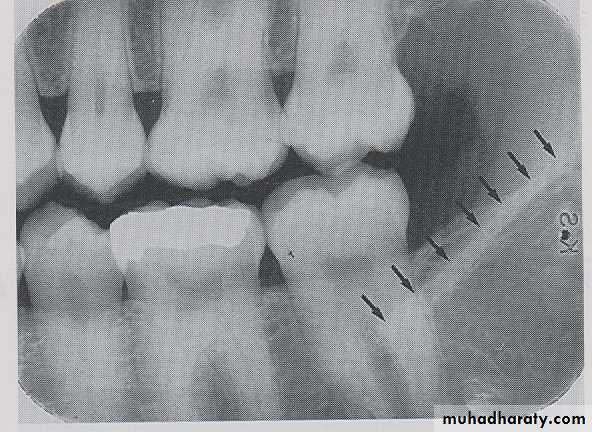

MYLOHYOID RIDGE

: The mylohyoid ridge is a linear prominence of bone located on the internal surface of mandible, its extended from the molar region downward and forward toward the lower border of mandibular symphysis and serves as the attachment site for the mylohyoid muscles. Radiographic appearance, mylohyoid ridge appears as a dense the radiopaque band that extends downward and forward from molar region.

SUB MANDIBULAR FOSSE:

Submandibular fosse is a scooped–out depressed area of bone located on the internal surface of mandible inferior to mylohyoid ridge. On periapical radiography the submandibular fosse appears as radiolucent area in the molars region below the mylohyoid ridge.